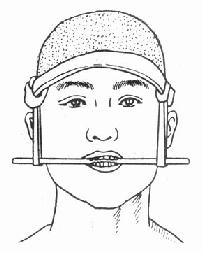

3.上颌骨骨折段下垂移位的伤员,在迅速清除口内分泌物或异物后,可就地取材采用筷子、小木棒、压舌板等,横放在两侧前磨牙部位,将上颌骨向上提,并将两端固定于头部绷带上(图4-2)。通过这样简单的固定,即可解除窒息,并可达到部分止血的目的。

图4-2 上颌骨骨折临时固定法